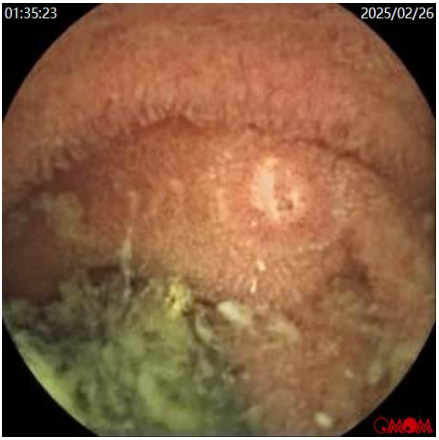

胶囊内镜(图5

小肠多发溃疡、糜烂:小肠淋巴管扩张?

图5a  胶囊内镜示小肠见白色绒毛样改变,小肠糜烂

图5b  胶囊内镜示小肠阿弗他样溃疡